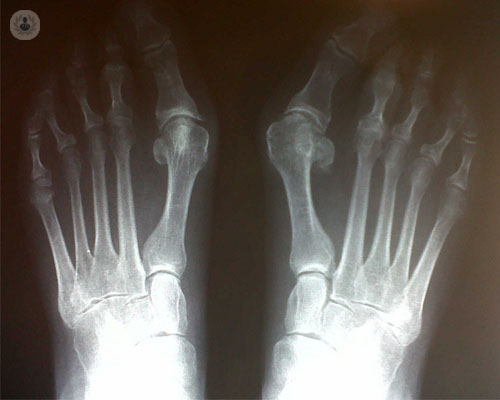

Cirugía del pie mínimamente invasiva

¿Qué es la cirugía del pie mínimamente invasiva? ¿Cuáles son las patologías más comunes en los pacientes? ¿Cómo se aplica? El Dr. Rabat, especialista en Traumatología, nos responde a estas preguntas explicando la evolución de la cirugía del pie y apuntando cómo podemos prevenir posibles lesiones.